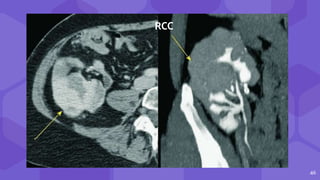

RCC PTLD

RCC

same appearance in native and